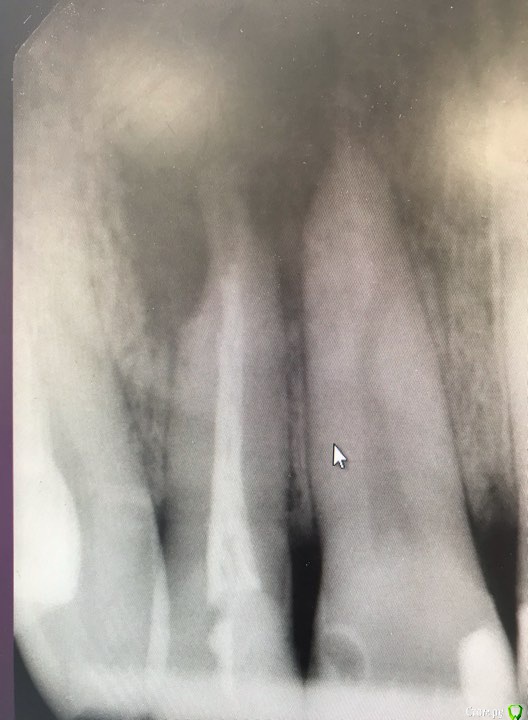

32worldwide Опубликовано 27 марта, 2019 Поделиться Опубликовано 27 марта, 2019 (изменено) Коллеги, на дляъ пришел пацуиент с пероститом в области 12 зуба. Пт-у уже были назнечены атибиотики, я расрыл абсцесс, спусти два дня жалоб у пациента нет. В дальнейшем планирую перелечить канал и сделать резекцию верхушки. Есть пара вопросов- через какое время после перелечивания можно приступать к резекции? Нужно ли ретроградно пломбировать корень? Спасибо за внимание и ответы! Изменено 27 марта, 2019 пользователем 32worldwide Ссылка на комментарий

___49___ Опубликовано 27 марта, 2019 Поделиться Опубликовано 27 марта, 2019 Без КТ резекцию не стал бы планировать, как red_butler заметил проверка на витальность вовлеченных в процесс зубов(см КТ), ну и предупреждаем пациента , что у него резорбция корней - как следствие процесс этот может не остановиться после РВК и зубы все равно будут потеряны (пациент проинформирован - подпись ) , ретроградка (как сказала annda )с МТА обязательно (тем более при резорбции) сошлифовать поверхностно весь дентин вовлеченный в процесс . Ссылка на комментарий

32worldwide Опубликовано 5 мая, 2019 Автор Поделиться Опубликовано 5 мая, 2019 Закончил перелечивание к/к (bioroot +gutta #30). У пациента жалоб нет, пальпация в проекции верхушки безболезненна. Резекцию назначил на конец мая. Откровенно говоря будет первая такая операция у меня.. хочу услышать ваше мнение сколько мм корня убирать? Ссылка на комментарий